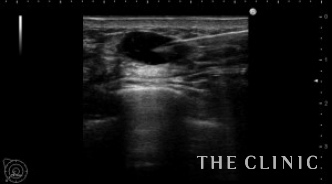

エコーでは多数のヒアルロン酸のしこりを認め、皮膚の発赤部分の深部は炎症のため診断できませんでした。

ヒアルロン酸注入によるしこりのエコー診断カルテ